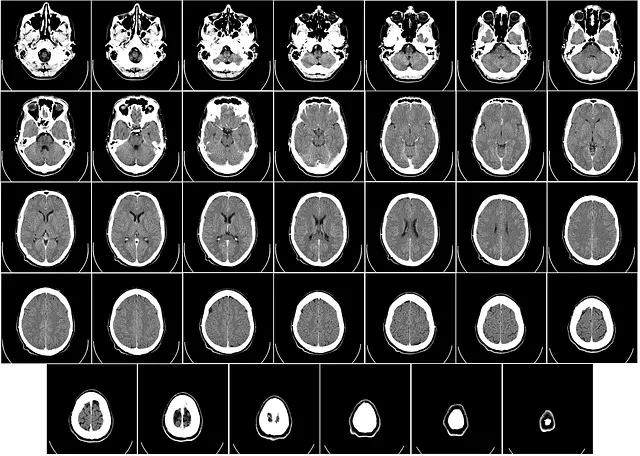

CT촬영이란?

CT촬영은 Computer Tomography의 약자로 우리말로하면 전산화 단층 촬영이라고 합니다. 즉 방사선을 신체에 투과하여 혈관이나 뼈 등 인체조직을 살펴보는 방사선 검사 방법입니다. 조금 더 구체적으로 말하면 정상 조직과 병변 조직을 구분하는 목적이 있습니다. 엑스레이는 단면을 찍지만 CT촬영은 연속적으로 사진을 촬영하기 때문에, 더 세밀하며 입체적인 분석이 가능합니다. 때문에 골절, 혈관 그리고 종양 검사 등 아주 광범위하게 쓰이고 있습니다.

비슷하게 생긴 장비의 MRI와는 달리 몸안에 금속이 있어도 검사가 가능하며, 신체의 데미지 없이 신체 상태를 파악하는 것이 장점입니다. 데미지가 없기 때문에 통증은 없으나, 엑스레이보다는 노출되는 방사선량이 많습니다.

CT촬영의 대표적인 검사 부위 및 질환으로는 표를 참고해주세요.